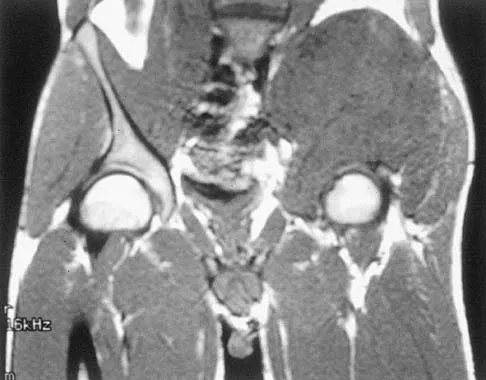

A 25-year-old man has had an insidious onset of left hip pain over the past 11 months. A radiograph, coronal MRI scan, and histopathologic specimens are seen in Figures 2a through 2d. What is the most likely diagnosis?

Explanation

Ewing's sarcoma is the second most common primary sarcoma of bone in children and young adults. It is a malignant round cell tumor with uncertain histogenesis. Sheets of uniform small round blue cells with a high nuclear-to-cytoplasm ratio and the absence of osteoid formation differentiate this histologic diagnosis from the other conditions. Immunohistochemical staining and molecular diagnostic studies are useful to verify the diagnosis.